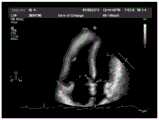

FIG. 6 is a schematic diagram of a thermodynamic diagram of a cardiac anatomy predicted by an anatomy recognition model provided by an embodiment of the present application;

Next, the cardiac ultrasound image to be identified is input into the above-mentioned anatomical structure identification model trained in advance, and the anatomical structures in the image are predicted by using the model, so as to obtain a thermodynamic diagram corresponding to each anatomical structure, and at this time, the prediction output result of the model is shown in fig. 6.